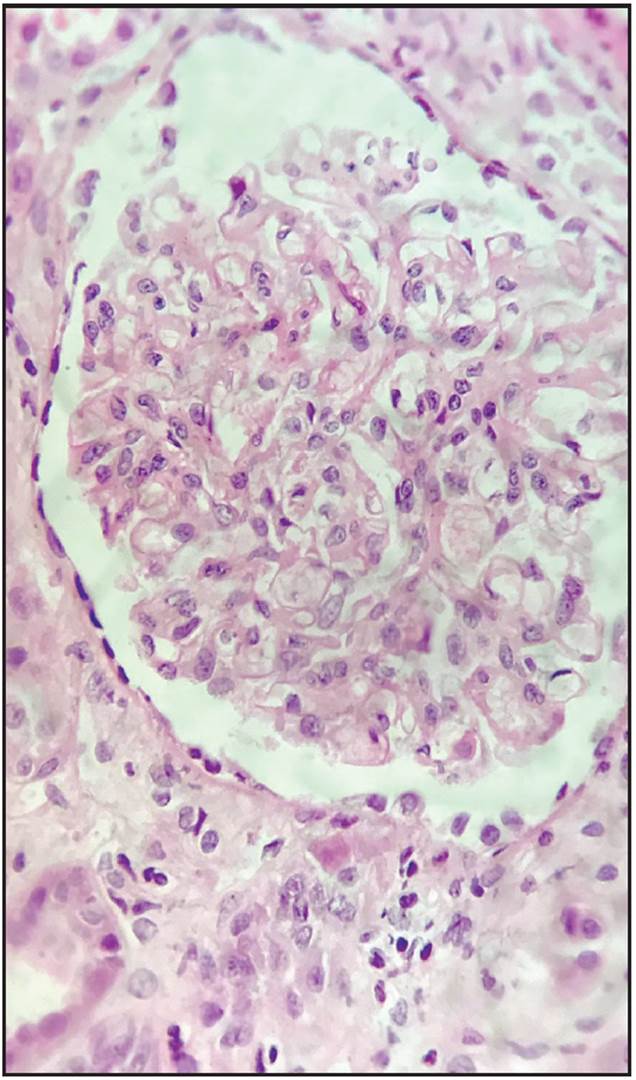

En su reporte se informa que se obtuvieron 20 glomérulos, en cinco había esclerosis global, sin alteraciones en mesangio, membranas basales glomerulares, ni cambios inflamatorios en glomérulos (Figuras 1 y 2). Atrofia tubular de 5%, sin compromiso inflamatorio intersticial, vasos sanguíneos con engrosamiento miointimal y cambios hialinos de la pared muscular con ligera estrechez de la luz (compatible con nefroesclerosis hipertensiva). Inmunofluorescencia negativa para depósitos de complejos inmunes, complemento (C3, C4, C1q), fibrina y cadenas ligeras de inmunoglobulinas. En la microscopia electrónica o análisis ultraestructural los principales hallazgos estaban en los podocitos, con pérdida de pedicelos (sus pies) en el 70% de la superficie capilar, y presencia de numerosos cuerpos de cebra o lamelares correspondiente a inclusiones lisosómicas en su interior (Figuras 3 y 4).

Figura 1 Microscopía de luz 10x. Gloméinlos normales, 1 esclerosado. Túbulos e intersticio normales.